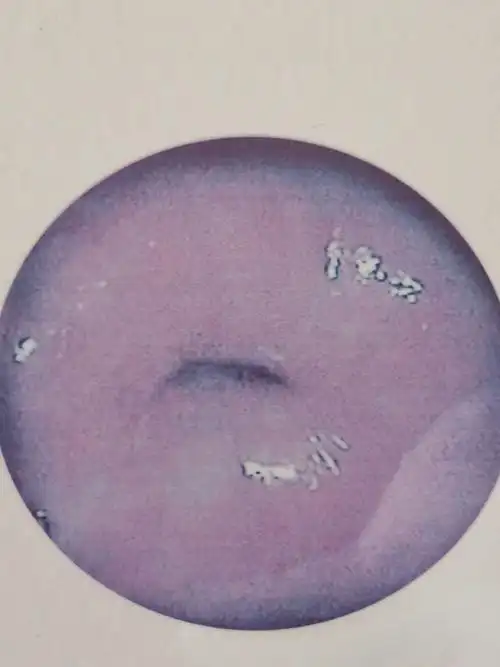

宫颈糜烂莫惊慌,治亦观察需辨别

宫颈糜烂

肉眼可见宫颈自内口向外呈红色颗粒状,根据面积不同分为Ⅰ度,Ⅱ度及Ⅲ